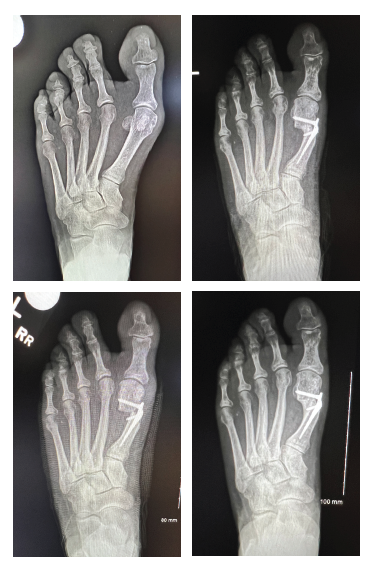

Tricortical radiographic consolidation on two orthogonal radiographs mark achievement of bony consolidation. Computed tomography may be necessary to confirm complete osseous healing in foot and ankle cases. Obtaining this endpoint then allows for removal of the external fixation.

Other reported complications include joint stiffness and subluxation, as well as osseous malalignment. During lengthening, there is a tendency for the bone segment in question to gradually veer off its intended course due to muscle forces or instability secondary to an inadequate external fixator construct.2,9,10 Other complications relate to the consolidation rate at the distraction site. Premature consolidation occurs as a direct result of an excessive latency period in which significant callus healing blocks the distraction. In contrast, prolonged or delayed consolidation can occur secondary to patient metabolic, environmental, or technical factors including: poor osteotomy technique, initial diastasis, or rapid distraction.9,10 Pin site tract infections, fracture after external fixator removal, and chronic regional pain syndrome have also been reported.19

3. Lamm BM. Percutaneous distraction osteogenesis for treatment of brachymetatarsia. J Foot Ankle Surg. 2010;49:197-204.